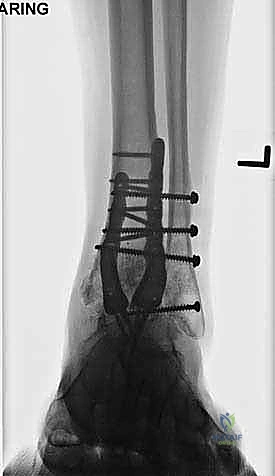

- الأشعة السينية أثناء الوقوف (Weight-bearing X-rays): هي الفحص الذهبي والأهم. يجب أن تؤخذ الأشعة والمريض واقف لتحمل الوزن. تظهر الأشعة تضيق المسافة المفصلية (دليل على فقدان الغضروف)، وجود نتوءات عظمية، تصلب العظم، وأي انحراف في محور المفصل.

لماذا المدخل الأمامي (Anterior Approach)؟

- تثبيت ميكانيكي حيوي أقوى: يتيح المدخل الأمامي وضع شريحة معدنية (Anterior Plate) على الجانب الأمامي للمفصل. من الناحية الميكانيكية الحيوية (Biomechanics)، يعتبر الجانب الأمامي هو "جانب الشد" (Tension side) أثناء المشي. وضع الشريحة هنا يوفر تثبيتاً فائق القوة ويقلل من معدلات عدم الالتئام.

- التخطيط الجراحي الرقمي: باستخدام صور الأشعة المقطعية، يقوم الدكتور هطيف بتخطيط الجراحة على الكمبيوتر لاختيار حجم المسامير والشرائح المناسبة بدقة مليمترية.